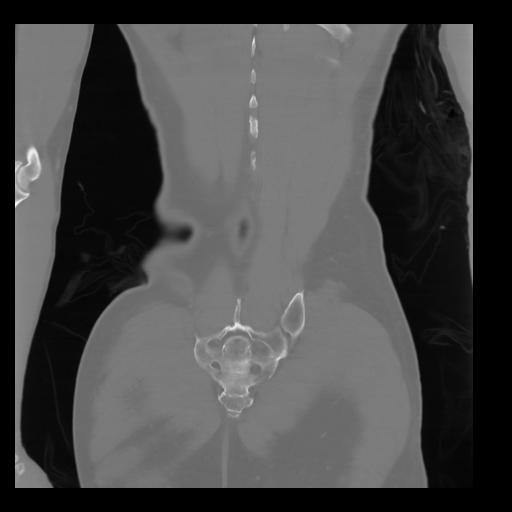

35 CUERPO,CE,Coronal,3.000,CUERPO,Coronal,